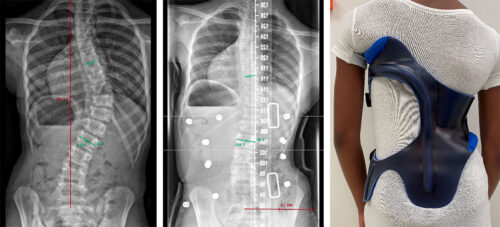

ماذا تقول الدراسات الطبية الحديثة؟

أثبتت عدة دراسات دولية فعالية الحزام الطبي، ومن أبرزها:

أن ارتداء الحزام لمدة 23 ساعة يوميًا يُعد الخيار الأكثر فعالية مقارنة بالمراقبة أو التحفيز الكهربائي.

تحليل تلوي لـ20 دراسة أكّد أن مدة ارتداء الحزام مرتبطة مباشرة بنسبة النجاح، حيث كانت النسبة الأعلى لمن يرتدونه لأكثر من 20 ساعة يوميًا.

مراجعة منهجية حديثة خلصت إلى أن الحزام الطبي يساعد على الحد من تفاقم الجنف على المدى الطويل، مع وجود تباين في القدرة على تقليل الحاجة للجراحة.

هل يمكن تجنّب الجراحة باستخدام الحزام فقط؟

في كثير من الحالات، نعم. تشير الدراسات إلى أن العلاج بالحزام يقلل من احتمال الحاجة إلى الجراحة، خاصة عند استخدامه مبكرًا مع التزام كامل بخطة العلاج.

تُظهر الأدلة أن الحزام خيار فعّال وموثوق في علاج اعوجاج العمود الفقري، خاصة في حالات الانحراف القطني والصدري السفلي. كما تُشير النتائج إلى أن الحزام لا يُستخدم فقط لتقويم الانحناء، بل يساهم أيضًا في تحسين التوازن الجسدي والمظهر العام.